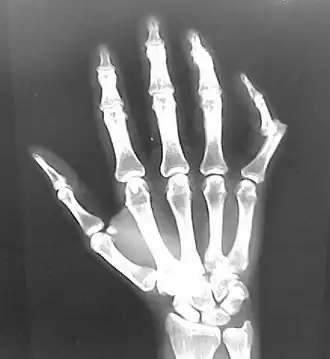

Radiograph of right fifth finger dislocation

X-ray, usually a minimum of 2-views

• Generally, pre- and post-reduction X-rays are taken. Initial X-ray can confirm the dislocation and evaluate for any fractures. Post-reduction x-rays confirm successful joint alignment and can identify any injuries that may have been caused during the reduction procedure.[17]